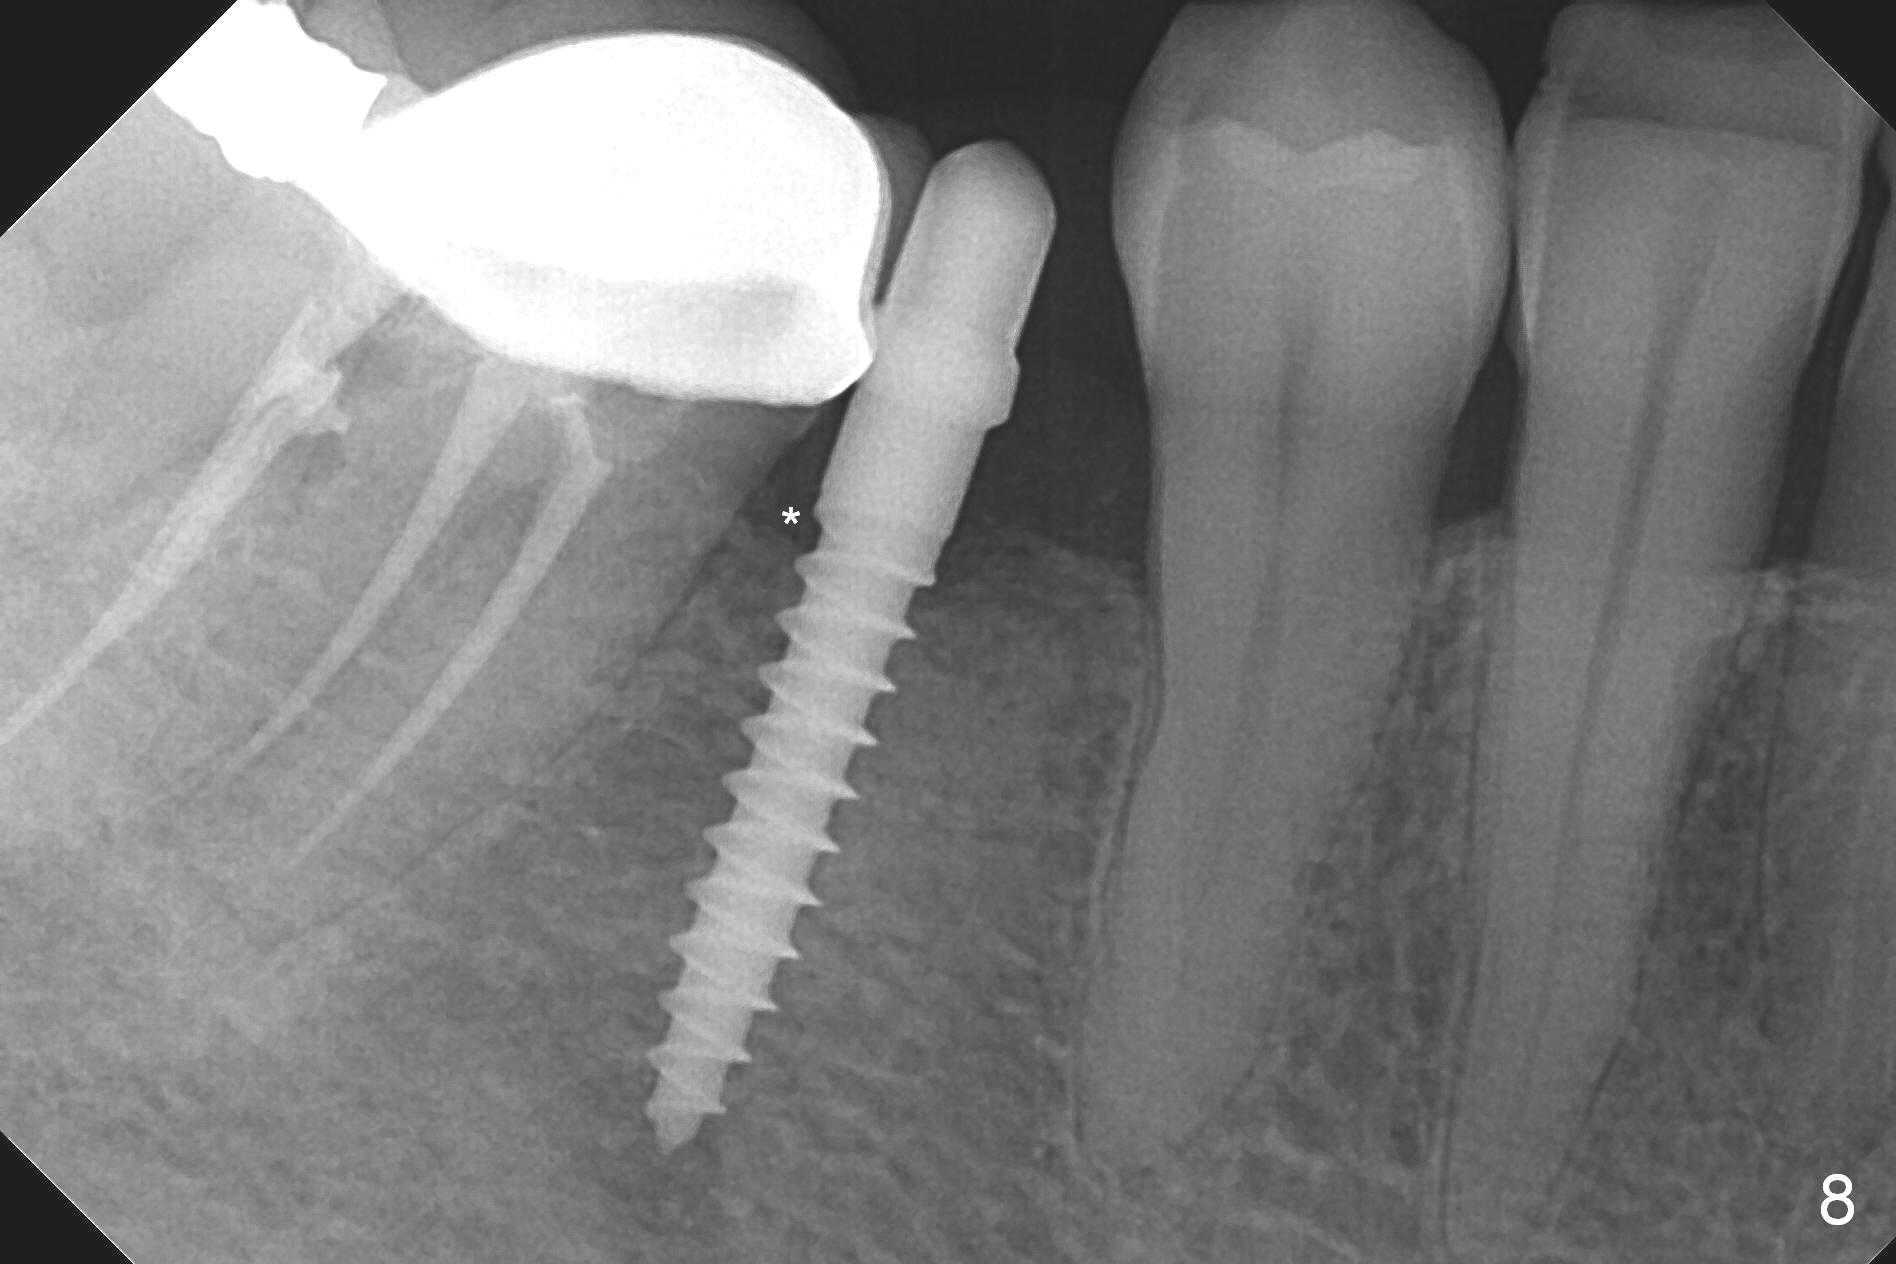

Preop photo shows the distal inclination of the tooth #28 (Fig.1). The distal surface of the latter is reduced before incision for implant placement at #29 (Fig.2). The buccolingual width is approximately 4 mm, as compared to 3 mm implant positioner (Fig.3). After 1.2x10 mm osteotomy (Fig.5), the mesiodistal cortical bone is removed with a small high-speed fissural bur (Fig.4). When a 2.5x12(2) mm 1-piece implant is placed (Fig.6), there is no buccal (Fig.7) or lingual plate perforation. There is no postop paresthesia. There is mild bone loss distal 4 months postop (Fig.8 *). Take photos before and after permanent crown cementation to show increase in ridge width after bone graft and improvement in gingival health after provisional modification. Take PA and/or BW post cementation to show that the distal bone resorption (Fig.8 *) is partially due to angulation. No continuous bone loss 15 months post cementation (Fig.9). There is mild bone resorption mesially 2 years 3 months post cementation (Fig.10). The soft and hard tissues remain healthy 4 years 3 months post cementation (Fig.11,12).